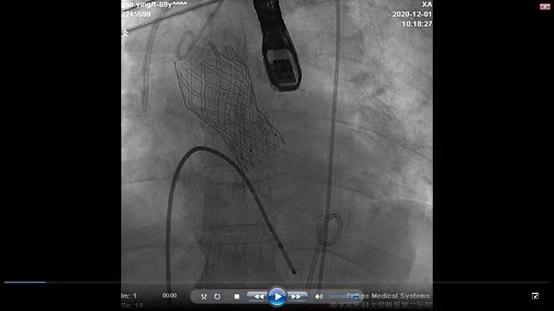

主动脉人工瓣成功植入

哈医大二院心内科TAVR团队进行了评估,认为张大爷符合TAVR手术指征。 经过与家属的充分沟通后,手术如期举行。哈医大二院心内科TAVR团队张东会医生、杨光医生、陈涛医生,三人通力协作,在超声医学科、麻醉科等学科配合下,独立完成了穿刺双侧股动脉入路,并将经导管成功置入人工主动脉瓣。手术历经2小时,顺利结束,张大爷心功能明显改善,无任何不适症状。术后第二天复查心脏彩超心脏收缩功能完全恢复正常,张大爷可以下地自由活动。